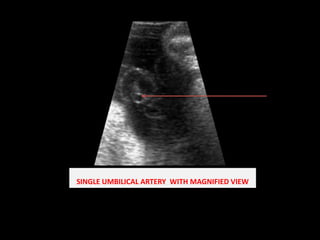

SINGLE UMBILICAL ARTERY  WITH MAGNIFIED VIEW